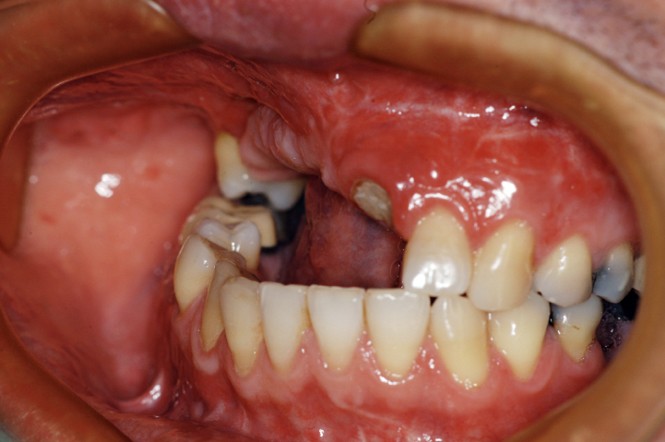

Car ce sont bien des situations cliniques exceptionnelles que ce conférencier a prises en charge, non pas seul, mais en constituant une équipe multidisciplinaire plus à même de relever les défis fonctionnels, structurels, biologiques et esthétiques en présence. Après avoir passé en revue les composants essentiels à l’obtention d’un sourire équilibré, Nadim Aboujaoude a évoqué les travers des traitements dits esthétiques mais conduits sans planification globale et qui engendrent des résultats disgracieux. Depuis de nombreuses années, l’engouement pour les solutions esthétiques ne faiblit pas. La divulgation médiatique des progrès technologiques et chirurgicaux réels encourage une part croissante de la population à recourir à des procédures souvent fiables, mais parfois portées au-delà des limites raisonnables. Ainsi, des traitements de médecine esthétique inadaptés engendrent un effet de « ligne de sourire basse » accompagné d’une exposition exagérée des incisives mandibulaires.

La demande de correction de cette anomalie esthétique incite les patientes à rechercher une compensation prothétique (à travers un abaissement des bords incisifs maxillaires visant à rendre sa visibilité au groupe incisivo-canin maxillaire) qui concoure à recomposer les rapports des étages de la face (en minorant l’étage inférieur et majorant l’étage moyen). La reprise de ces cas cliniques se révèle particulièrement délicate et repose sur une analyse rigoureuse des clefs esthétiques de l’harmonie du sourire et de son rayonnement au sein du visage.

Concernant le versant orthodontique des traitements multidisciplinaires, Nadim Aboujaoude intègre cette thérapeutique moins invasive à ses traitements multidisciplinaires sans rechercher une occlusion de classe 1 mais en privilégiant l’obtention de situations facilitant les solutions prothétiques, parodontales ou implantaires : en redistribuant et optimisant les espaces prothétiques, en corrigeant les malpositions dentaires, en remplaçant les dents compromises par les dents adjacentes, en harmonisant les contours gingivaux, en optimisant l’inclinaison des racines dentaires et en créant des volumes osseux favorables à la mise en place d’implants. À l’issue d’une présentation riche en prise en charge thérapeutique de cas complexes, le conférencier a clairement démontré que toute solution thérapeutique ne peut se concevoir et s’établir que dans une logique multidisciplinaire axée sur la concertation.